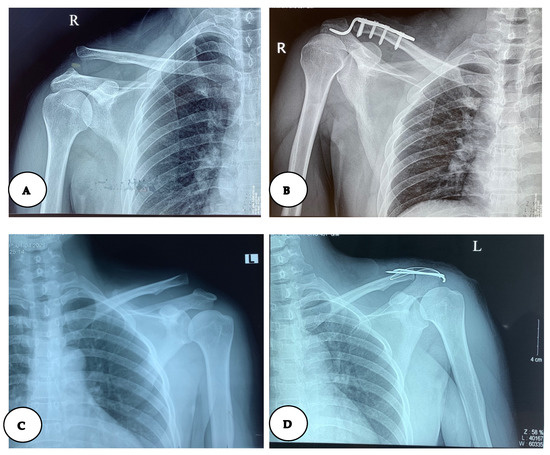

Surgical Techniques and Postoperative Care